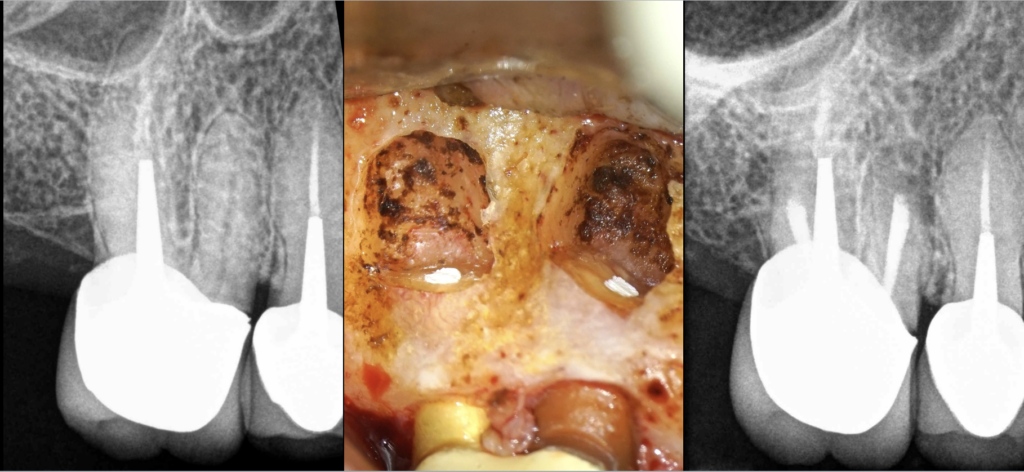

🦷 Cas clinique :

- 𝐏𝐮𝐥𝐩𝐞 𝐩𝐫𝐞́𝐜𝐞́𝐝𝐞𝐦𝐦𝐞𝐧𝐭 𝐭𝐫𝐚𝐢𝐭𝐞́𝐞 (en tout cas dans le canal P)

- 𝐏𝐚𝐫𝐨𝐝𝐨𝐧𝐭𝐢𝐭𝐞 𝐚𝐩𝐢𝐜𝐚𝐥𝐞 𝐬𝐲𝐦𝐩𝐭𝐨𝐦𝐚𝐭𝐢𝐪𝐮𝐞 (lésions apicales des racines MV DV)

- 𝐂𝐡𝐢𝐫𝐮𝐫𝐠𝐢𝐞 𝐞𝐧𝐝𝐨𝐝𝐨𝐧𝐭𝐢𝐪𝐮𝐞 des canaux 𝐌𝐕𝟏 𝐌𝐕𝟐 (ainsi que 𝐥’𝐢𝐬𝐭𝐡𝐦𝐞 les joignant) et 𝐃𝐕